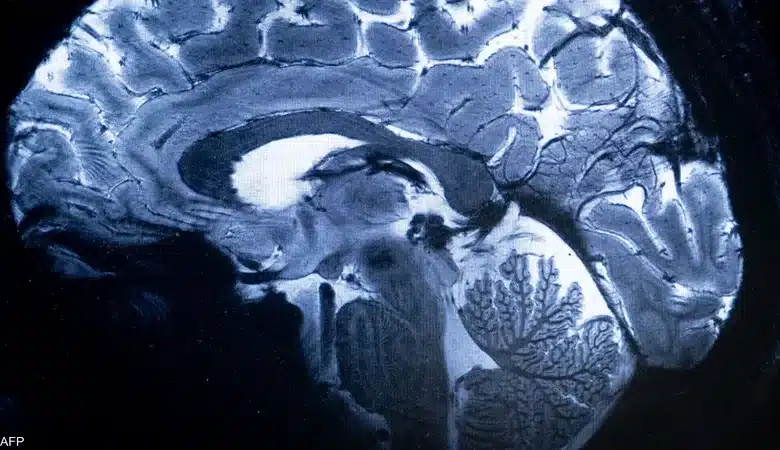

على مدى عقود طويلة، ظل العلماء يبحثون عن سر تخلص مخ الإنسان من النفايات التي يفرزها بشكل يومي أثناء التفكير والعمل العقلي، وهي فضلات تشمل بروتينات وجزيئات زائدة قد تتحول إلى مواد سامة إذا لم يتم التخلص منها، مثل بروتينات الأميلويد بيتا وتاو المرتبطة بشكل مباشر بمرض الزهايمر.

عام 2012، نجح فريق بحثي من جامعة روشستر الأميركية بقيادة الطبيبة مايكن نيدرغارد في اكتشاف نظام دوري غير معروف سابقًا يُطلق عليه “الجليمفاوي”، يعمل على طرد السموم من المخ. فقد أظهرت أبحاث على فئران التجارب تدفق السائل النخاعي عبر أنفاق تحيط بالأوعية الدموية، حيث يختلط بالسوائل الخلالية ويقوم بجمع الفضلات وحملها خارج المخ.

رغم أهمية هذا الاكتشاف، واجهت النظرية في بدايتها رفضًا من بعض العلماء، إذ تم التوصل إليها عبر أبحاث على الفئران، التي تختلف طبيعة نومها عن الإنسان. لكن خلال السنوات العشر الماضية، واصلت الدراسات العمل لإثبات وجود هذه الآلية لدى البشر، حتى جاء الدليل المؤكد أن المخ البشري أيضًا يغتسل أثناء النوم من خلال تدفق السائل النخاعي بدفع من الموجات الكهربائية العصبية.

بحسب جيفري إيليف، أستاذ طب النفس والأعصاب بجامعة واشنطن، فإن تعطّل النظام الجليمفاوي يؤدي غالبًا إلى تراكم البروتينات السامة، مما يرفع احتمالية الإصابة بأمراض عصبية ونفسية، وعلى رأسها الزهايمر. ويرى أن فهم هذا النظام يفتح الباب أمام تفسيرات جديدة لاضطرابات الشيخوخة والذاكرة.

تؤكد هذه الأبحاث أن النوم لا يقتصر على الراحة واختزان الذكريات، بل يمثل عملية تنظيف حيوية للمخ. فالجسم البشري ينتج ثلاثة إلى أربعة أضعاف مخزونه من السائل النخاعي يوميًا، والنوم هو المفتاح الأساسي لإدارته بكفاءة وطرد الفضلات السامة.